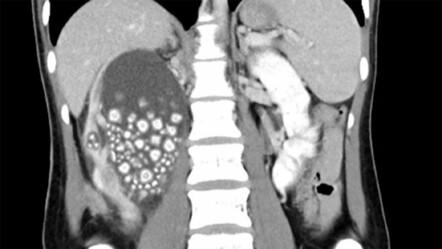

ZİYNETİ KOCABIYIK'IN HABERİ - Bütün dünyada ve ülkemizde inanılmaz bir hızla artan obezite, diyabet, hipertansiyon, kolesterol ve damar kireçlenmesi beşlisinin oluşturduğu yeni bir sendrom tanımlandı. ‘Kardiyorenal sendrom’ adı verilen bu yeni hastalıklar demeti, kalp ve böbreklerin birbirini etkilemesi sebebiyle her iki hastalığında daha kötü seyretmesine, ölüm oranlarının artmasına neden oluyor. ‘Kardiyorenal Sendrom’ durumunda; akut ve kronik kalp problemleri sonucunda böbrek fonksiyonları giderek bozuluyor, böbrek fonksiyonlarındaki bozulma ise kalp hastalıklarını olumsuz etkiliyor.

Vücudun biyokimyasal durumunun dengede olması gerektiğini söyleyen Türk Böbrek Vakfı Mütevelli Heyeti Üyesi Nefroloji Uzmanı Prof. Dr. Mehmet Şükrü Sever “Böbrek yetersizliği söz konusu olduğunda vücutta önce su birikmeye başlar. Bilinir ki diyalize giren hastalar hiç idrar yapamazlar. Kalp zaten fazla çalışan bir organken bir de fazla miktarda sıvı yükü ile karşı karşıya kaldığında kan tuzlarında dengesizlik ortaya çıkar. Böyle bir durumda çalışması iyice bozulur. Özetle kalp yeterince kan pompalayamazsa böbrek bozulur; böbrek yeterince süzemezse kalp bozulur. Bu ikisi yakın bir ilişki içindedir. O sebeple diyaliz hastalarında en önemli ölüm sebebi kalp yetersizliğidir” dedi.